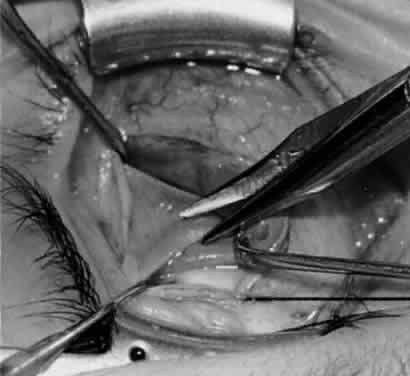

Fig. 12. An Aebli scissor is placed beneath the inferior oblique muscle insertion before it is sectioned from the globe.

Fig. 13. The inferior oblique muscle is sectioned from the globe. A preplaced 6-0 Vicryl suture is attached to the insertion.